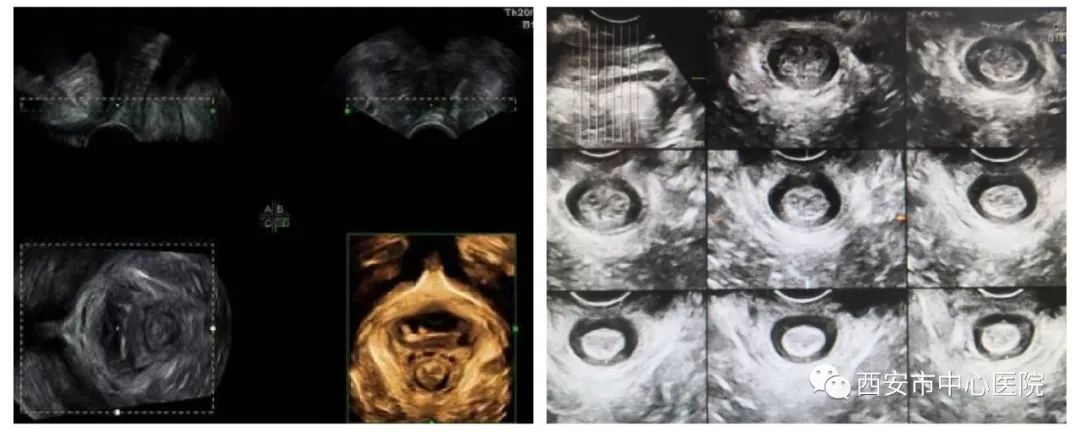

盆底超声包括二维超声检查盆底脏器有无脱垂及盆底四维成像检查盆底肌肉的完整性两部分。检查时将配备无菌保护罩探头放于会阴部,通过实时动态观察,比较患者静息、缩肛和Valsalva状态盆腔脏器结构和位置改变,直观反映子宫、直肠、膀胱等盆底器官的情况,可在临床症状出现之前做出早期诊断,为临床医生制定合理的治疗方案提供有力依据。

2) 能够多平面成像(可获得轴平面,这对于肛提肌评估是必要的);TUI成像模式观察肛门括约肌;

3) 可动态观察盆底变化(静息、缩肛及Valsalva动作)。

本科室拥有GE Voluson E10、E8高端四维彩色多普勒超声诊断仪,配备目前最先进的腔内四维、经会阴四维探头及软件,自动多层面TUI软件及增强技术,将盆底肌肉及韧带等结构清晰立体再现。